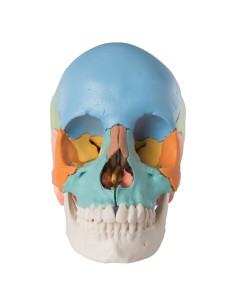

Dal cranio in 22 parti con incastri magnetici ai modelli di colonna vertebrale, da quelli di articolazioni a quelli di cuore, ogni pezzo della nostra collezione è progettato per un’immersione totale nello studio dell’anatomia umana. I nostri modelli, realizzati tramite scansioni di ossa vere, garantiscono un’esperienza tattile autentica e una fedeltà di peso quasi identica agli originali.

Essenziali per studenti e professionisti, i nostri modelli anatomici sono strumenti didattici che permettono di osservare le strutture anatomiche con precisione, eliminando la necessità di dissezioni o studi invasivi. Sono inoltre utili per spiegare ai pazienti le patologie, rendendo la comunicazione più efficace e risparmiando tempo prezioso.